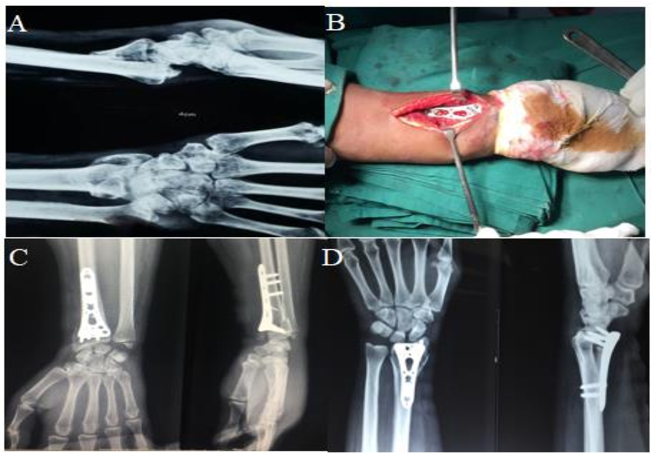

Pendant la chirurgie, la fracture est exposée et les fragments d'os sont réalignés dans leur position appropriée.Le plaque de verrouillage est ensuite positionné sur le site de la fracture et des vis sont insérées à travers la plaque et dans l'os pour stabiliser la fracture.Une fois la fracture solidement fixée, l'incision est fermée et le processus de récupération commence.

Plaque de verrouillage du radius distal VA : une solution avancée pour les fractures du poignet